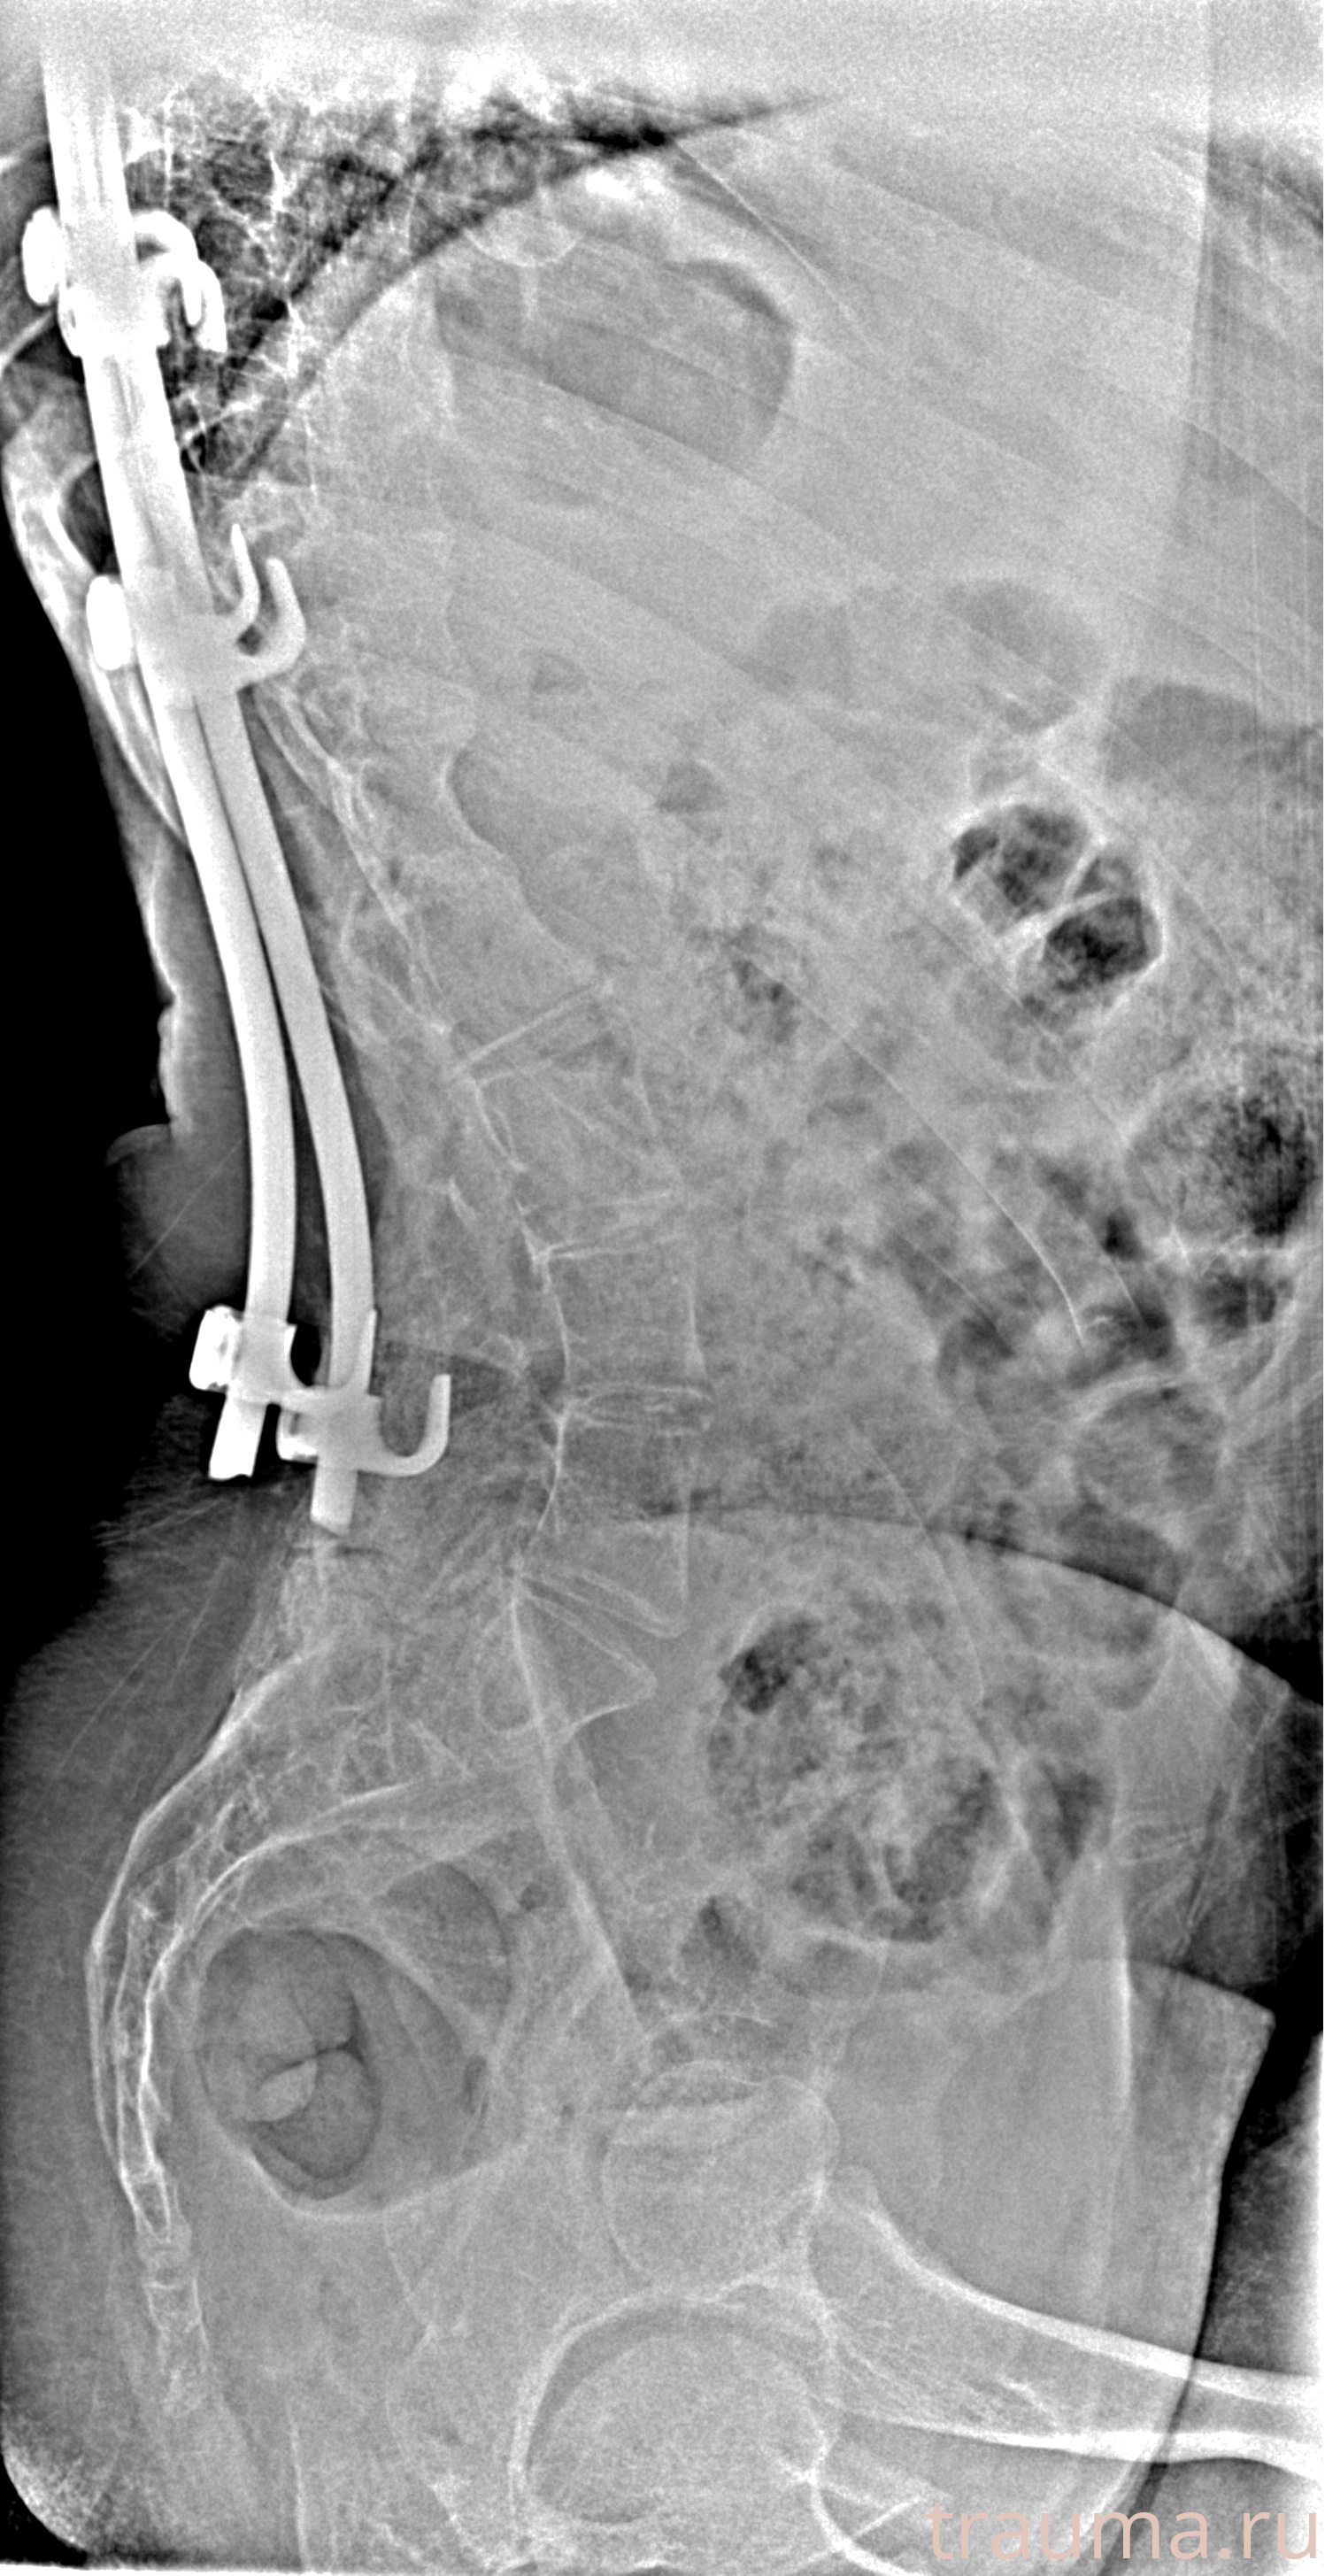

Рентгенограммы

Рентген на дому: по вашему адресу приезжает врач-рентгенолог, травматолог-ортопед с мобильным рентгеновским аппаратом, проводит диагностику травмы или заболевания, делает необходимые рентгенограммы, дает рекомендации по дальнейшему лечению. Получить качественные снимки в домашних условиях возможно благодаря уникальной методике, разработанной МосРентген Центром для института  Склифосовского